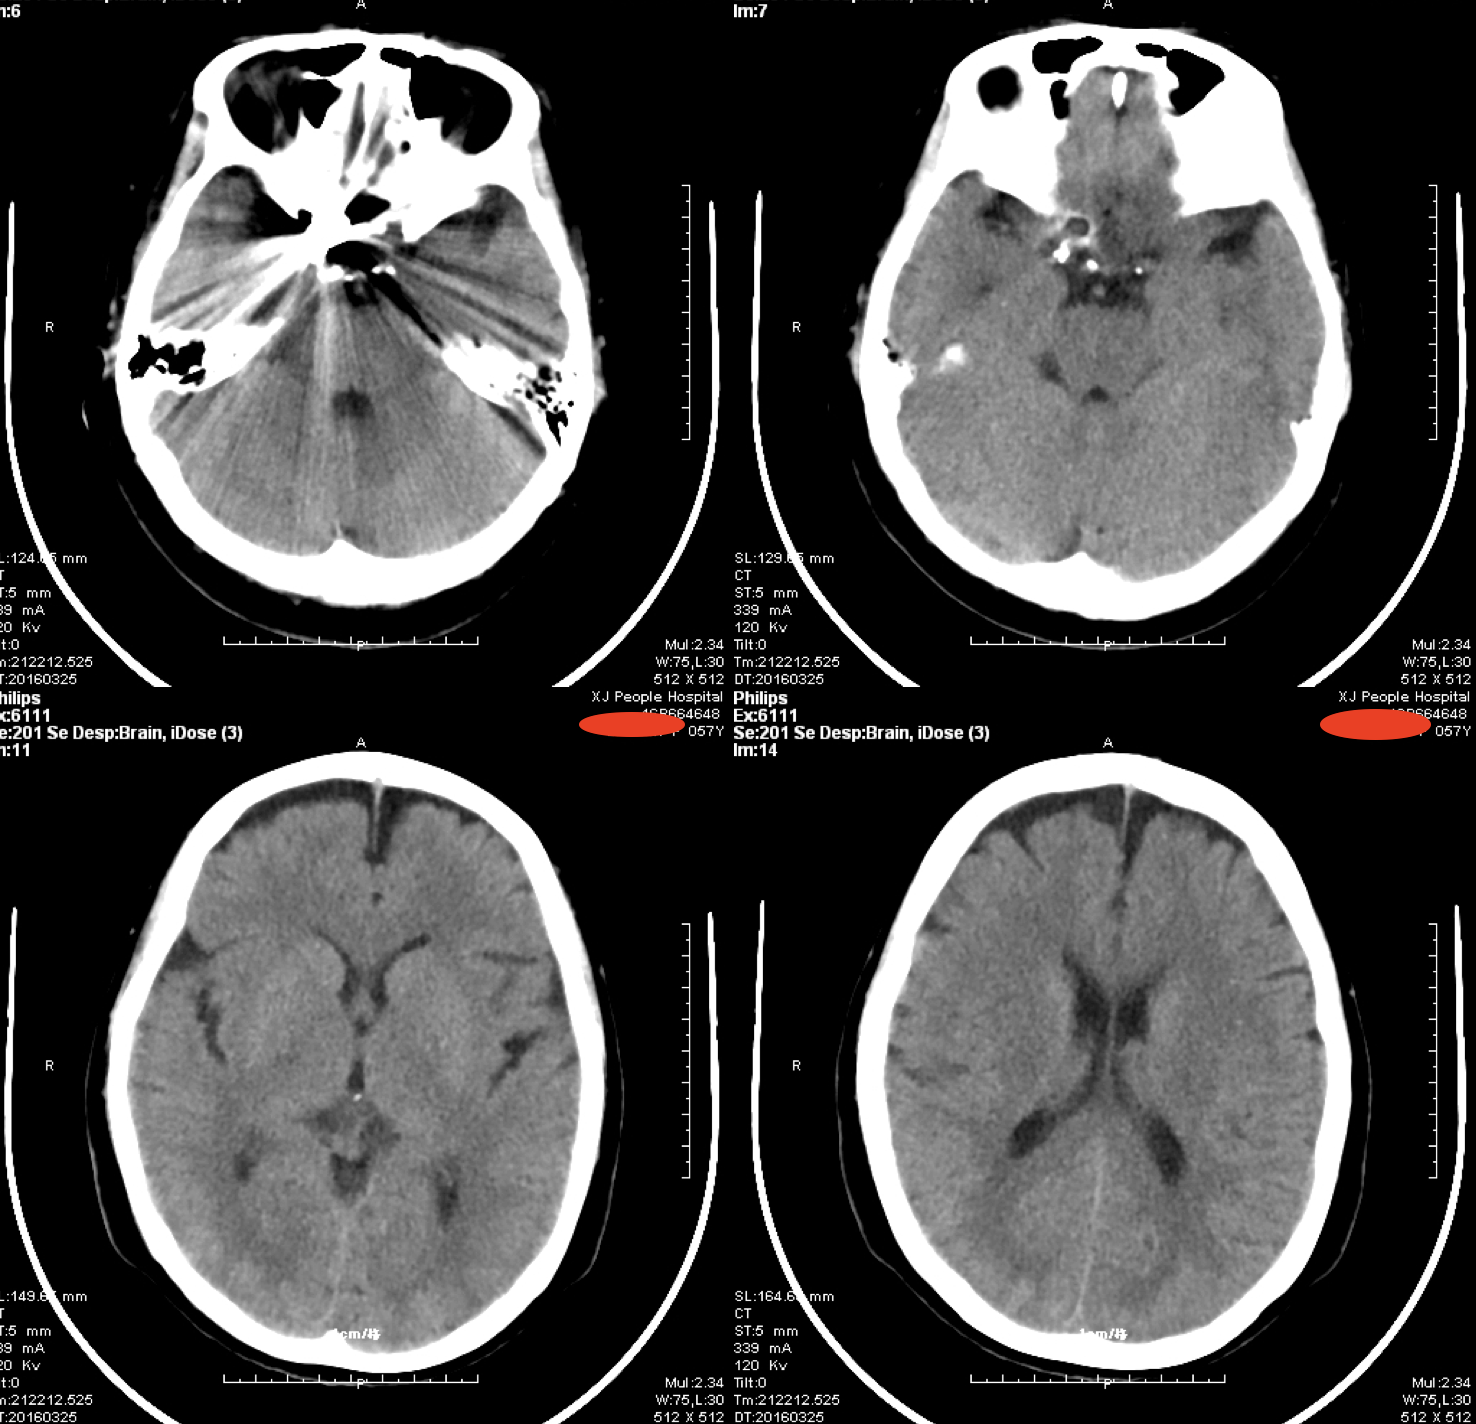

患者,女性,57岁,汉族,以“突发意识不清1次”收住神经内科。入院行头颅MR:右侧眼动脉段动脉瘤。进一步完善头颅CTA: 右侧眼动脉段动脉瘤。转入我科行动脉瘤栓塞治疗。

术后第二日头颅CT:颅内未见异常。患者术后无不适症状,恢复良好出院,继续口服双抗治疗。